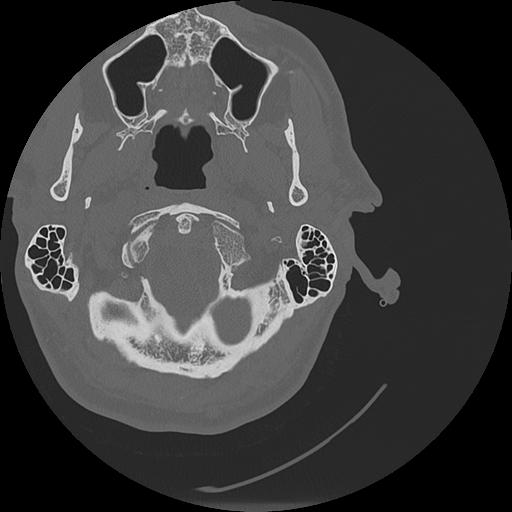

7 HUESO,,Vol,0.5,HUESO,,